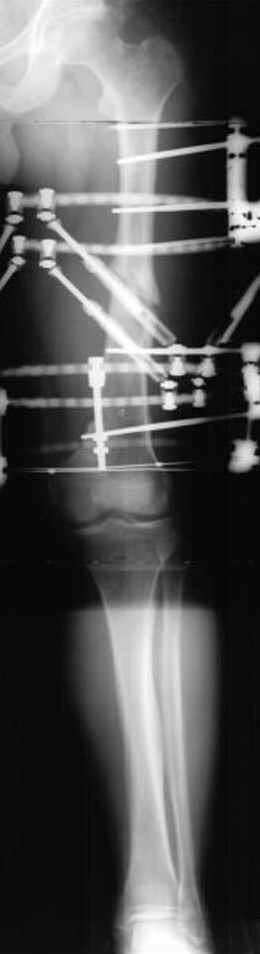

Если, например, доводится лечить больных с псевдартрозами шейки бедра, то надобность есть, и приходится. См. приложение.

Отправитель: Djoldas Kuldjanov 23 Ноябрь 2004, 18:21

пластическая модель; и коррекция бедра аппаратом Илизарова.

Имею другие снимки тоже, получится как отчет о моей работе.